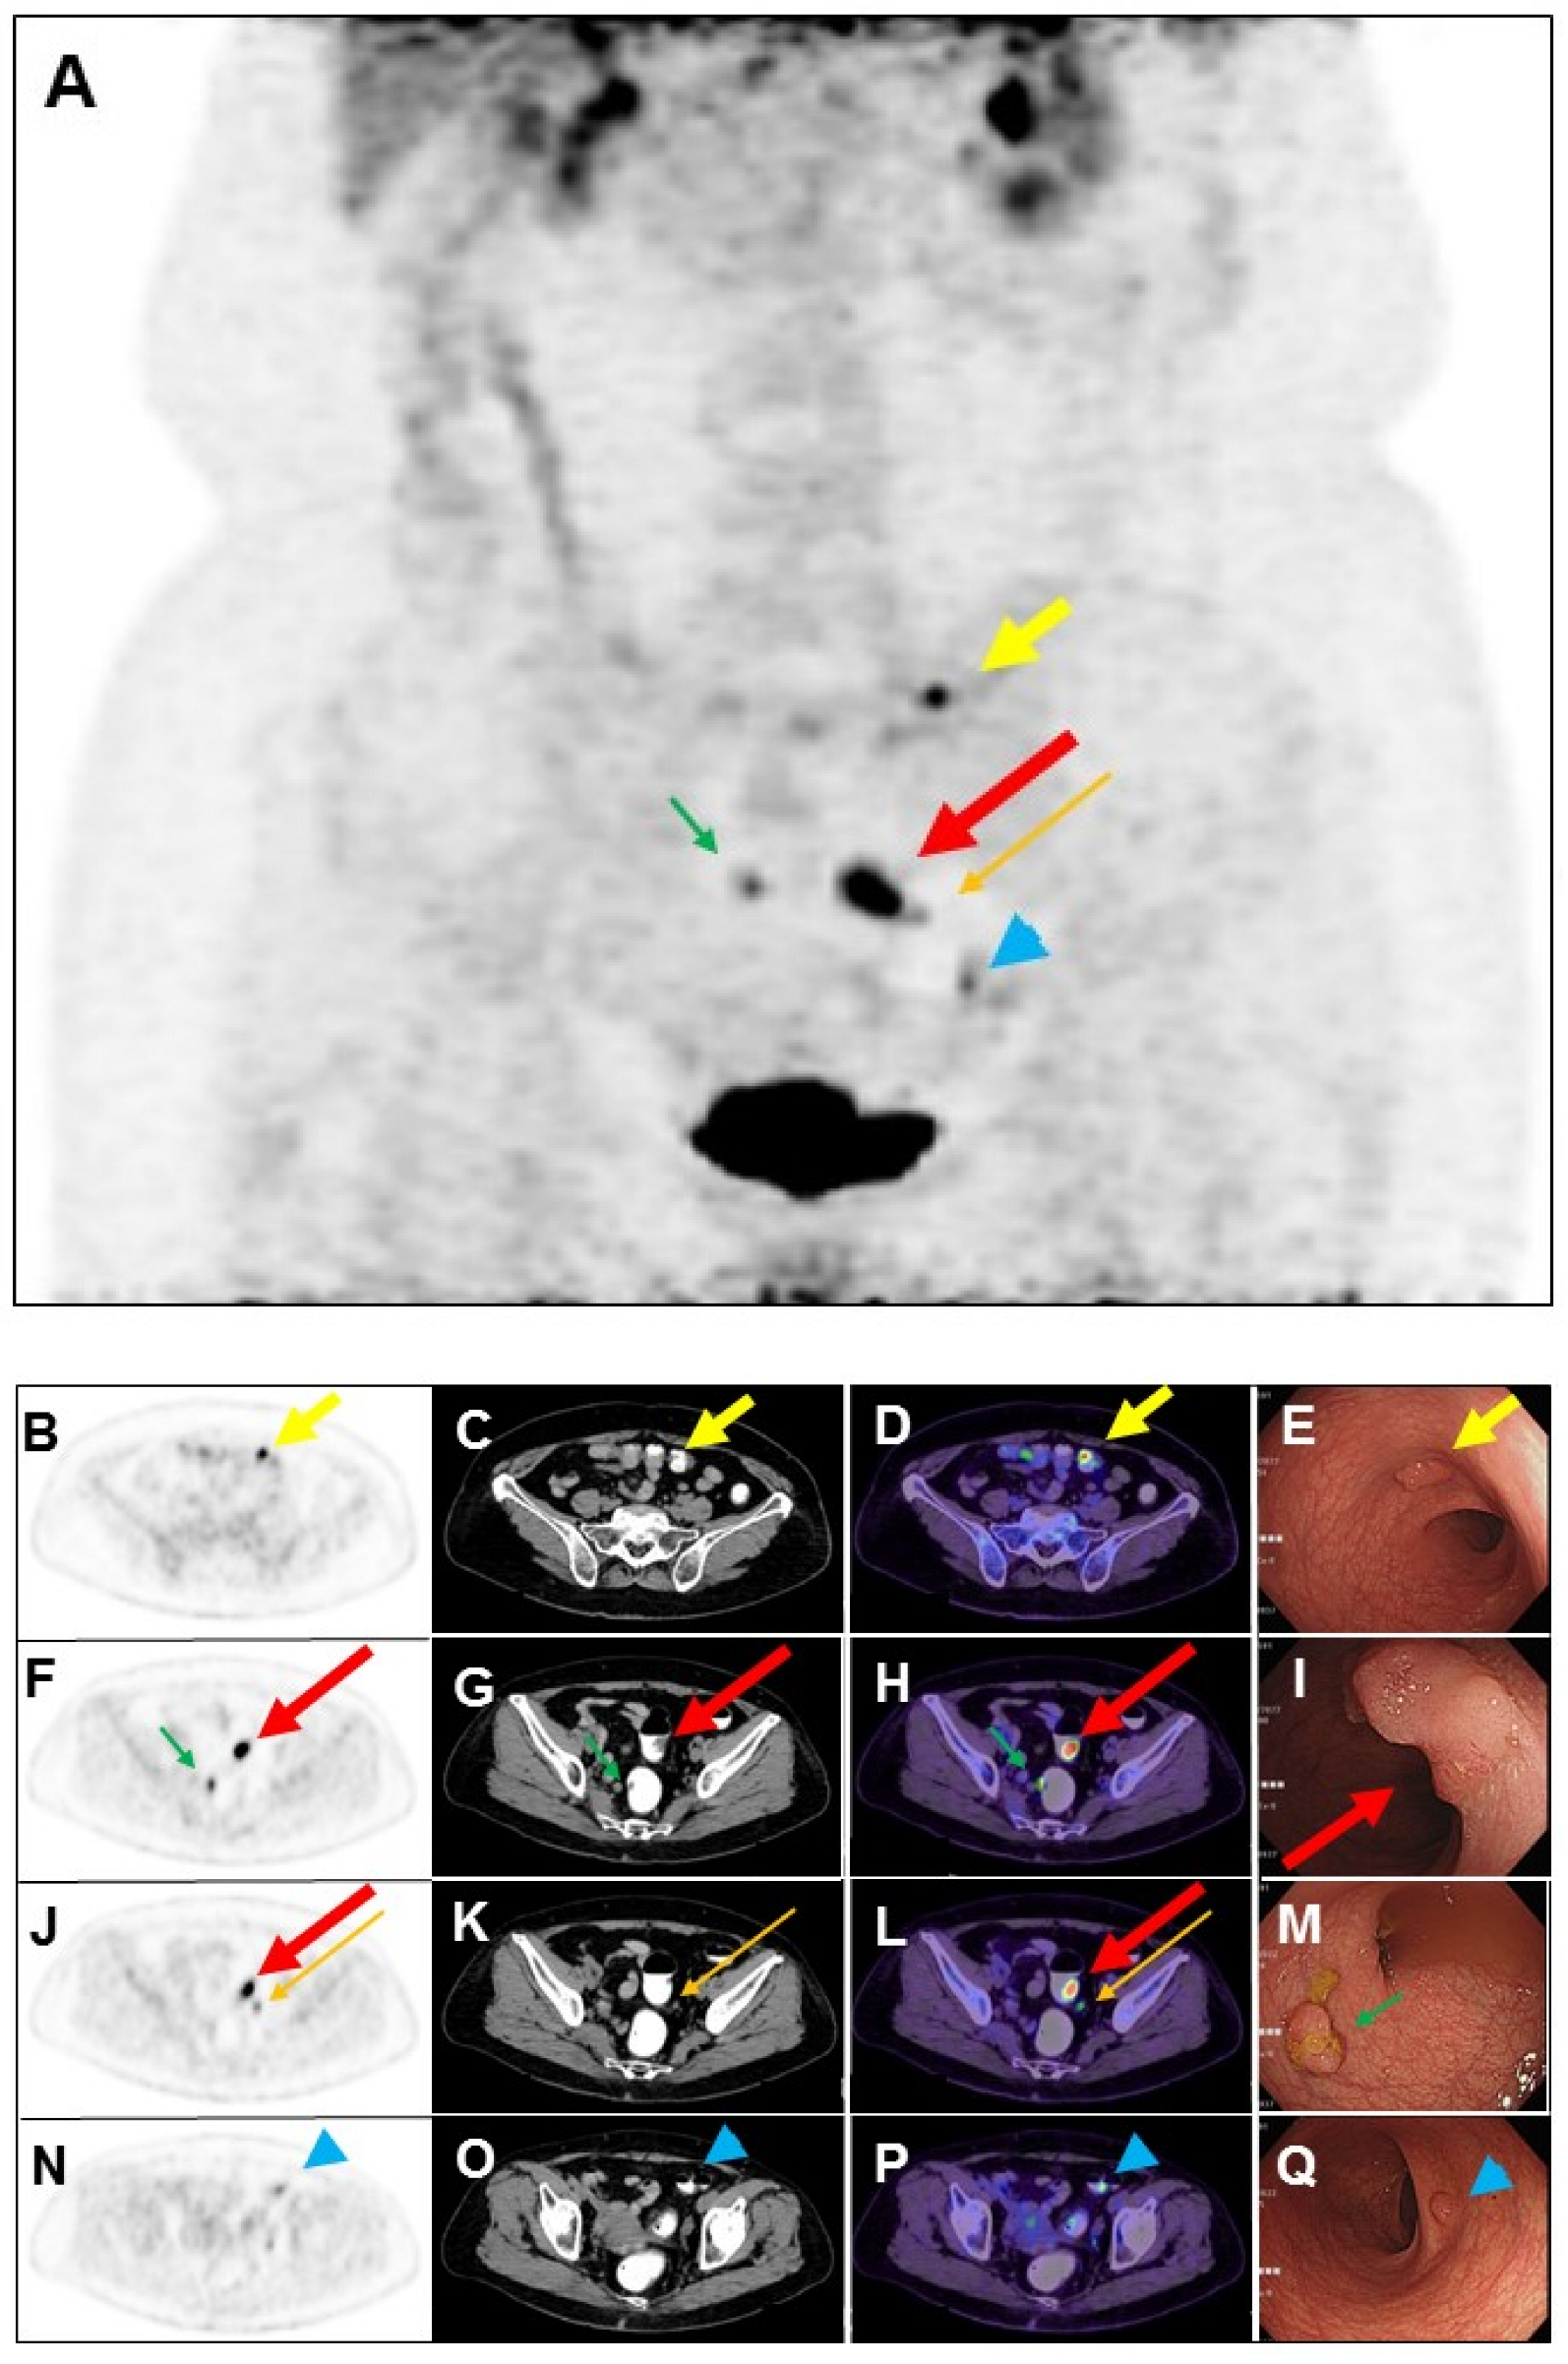

F-18 fluorodeoxyglucose (FDG) is excreted in part by the gastro-intestinal tract, with accumulation expected normally in the stomach and intestines. These physiologic sites of FDG accumulation may be confused with malignant lesions, and similarly increased FDG accumulation in malignant lesions may be interpreted as unrelated to cancer. A 75-year-old woman had a history of left breast adenoid cystic carcinoma following neoadjuvant chemotherapy and partial mastectomy. The pathology stage was pT2N0, and the Ki-67 index was 5%. Four years later, the patient’s left chest wall recurred and received excision. More than two weeks later, she received FDG positron emission tomography (PET)/computed tomography (CT) scan. The maximum-intensity projection view of PET image (A) revealed a focal intense FDG accumulation in the sigmoid (long thick arrow: red color), a focal mild FDG uptake in the pericolic lymph node (0.6 cm, long thin arrow: orange color), and a focal increased FDG accumulation in the transverse colon (short thick arrow: yellow color). Transaxial views of PET (B), CT (C), and PET/CT fusion (D) images showed a possible nodule in the sigmoid (long thick arrow: red color).